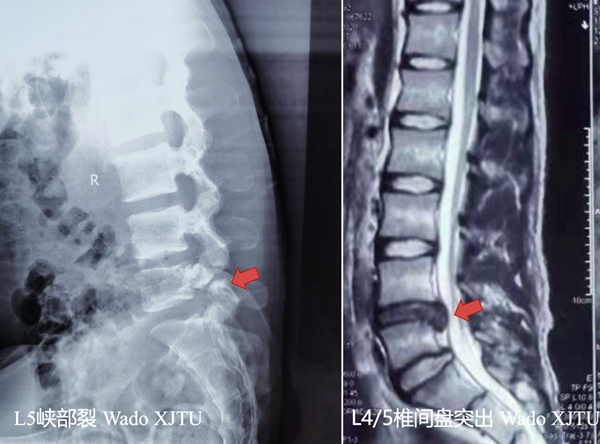

20岁男性患者,腰痛不适伴右下肢抽痛2月余,保守治疗效果不佳,慕名来到我院。骨二科王栋教授接诊了该患者,经过仔细询问病史及体格检查,完善相关影像学检查后,患者确诊为:腰椎间盘突出症(L4/5);腰5椎弓根峡部裂。

术前患者病变影像